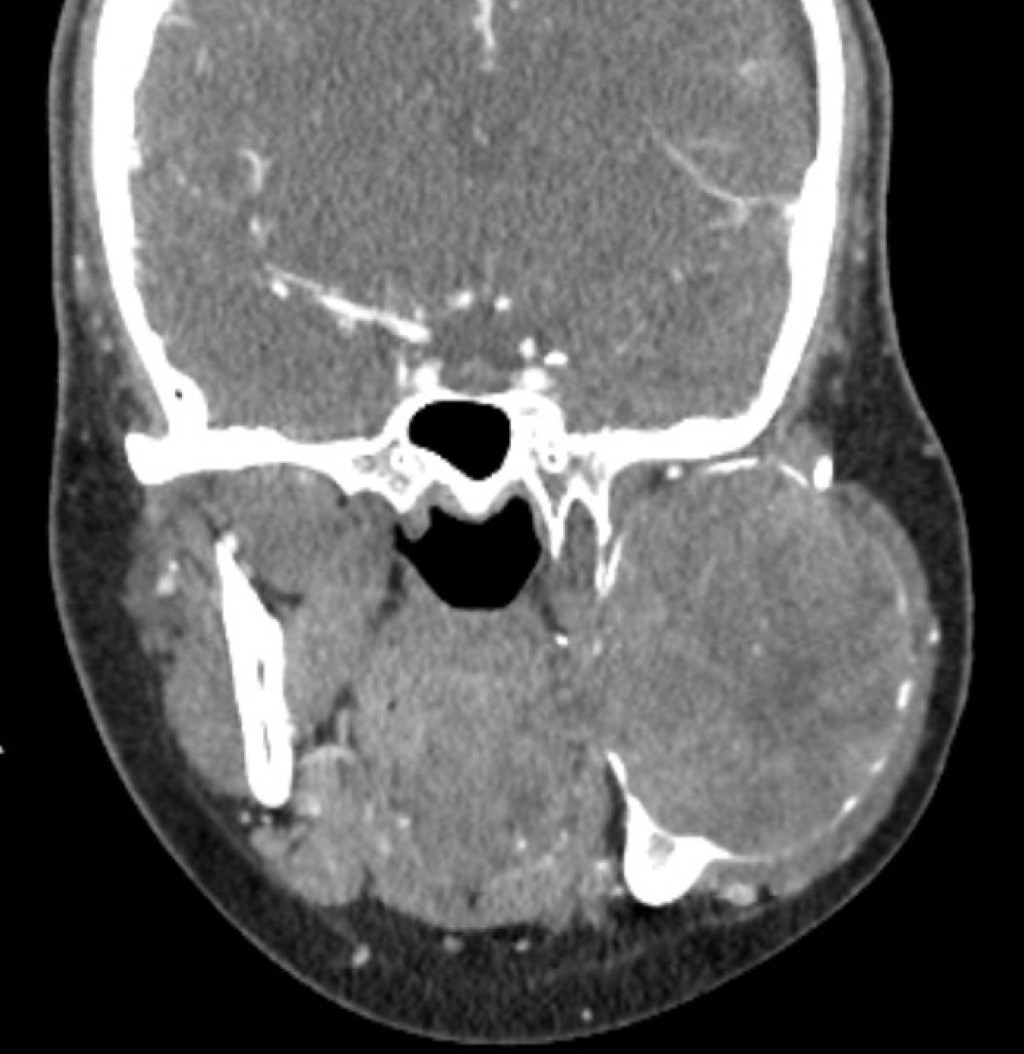

La tomografía contrastada mostró una lesión osteolítica bien delimitada con bordes escleróticos, afectando cóndilo, rama y cuerpo mandibular izquierdo posterior al primer premolar; la lesión medía 56 × 70 × 66 mm, con erosión del maxilar izquierdo y desplazamiento de arteria carótida externa y vena yugular interna (Figuras 2, 3, 4, 5 y 6).

Figura 2

Figura 3

Figura 4

Figura 5

Figura 6